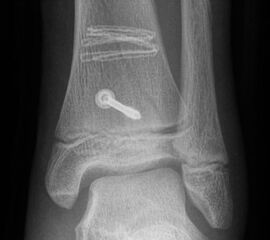

Die häufig nicht dislozierten knöchernen Ausrisse können konservativ behandelt werden. Dislozierte Fragmente sollten operativ mit Kirschner-Drähten oder Schrauben fixiert werden (Abb. 32). Die Nachbehandlung umfasst eine 4-wöchige Entlastung im US-Gips. Eine Röntgenkontrolle erfolgt nach Gipsabnahme. Freies Gehen sollte nach 6 Wochen möglich sein. Danach ist auch eine sportliche Belastung des Sprunggelenks möglich (v. Laer 2013).

Eingebrachtes Osteosynthesematerial sollte vor der Vollbelastung entfernt werden.